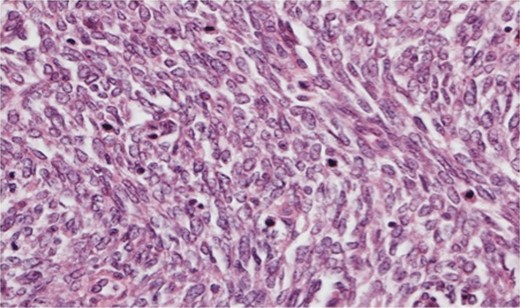

The histopathology demonstrated that the breast was partially replaced by a partly cystic and partly solid necrotic lesion. The cystic cavity contained blood clots. A microscopic examination showed an atypical undifferentiated spindle cell lesion with a fascicular architecture, pleomorphism and marked mitotic activity with areas of ulceration and necrosis (Figs 1 and 2). The initial set of immunostains performed showed that tumour cells were negative for cytokeratins (Fig. 3), S100 and LCA. The tumour cells showed diffuse and strong vimentin positivity (Fig. 4). Further immunocytochemical labelling showed weak expression of CD99, patchy strong expression of CD10 and patchy weak expression of smooth muscle actin. Cytokeratins (CAM 5.2) and EMA were expressed and there was no tumour-specific expression of CD34, desmin or myogenin. Fluorescent In-situ hybridization analysis failed to demonstrate evidence of a t(x:18) translocation using the LYS-SYT break apart probe. The diagnosis of a Grade 3 undifferentiated spindle cell sarcoma was made and although the tumour was reported to have a clear resection margin (5 mm) in most areas, the presence of necrosis and granulation tissue reaching the deep margin made the status of the margin uncertain.

Photomicrograph showing negative cytokeratin AE1/AE3 staining in spindle cells.